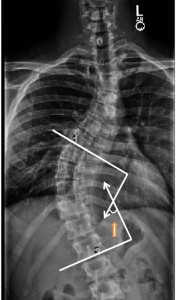

As I mentioned in my last post, I am also working on viewing x-rays in order to record radiographic measures. I have to look at the curve of the spine and the degree of pelvic obliquity both before and after surgery. It is very encouraging to see how a patient with a very severe curve will have an almost completely straight spine after fusion. Not only is it encouraging, but it also supports my desire to enter the medical field. Below are some photos of the radiographic measures I am referring to. (The x-ray isn’t a photo of measurements I have done myself because I don’t want to release any sensitive information, but, nevertheless, it gets the point across).